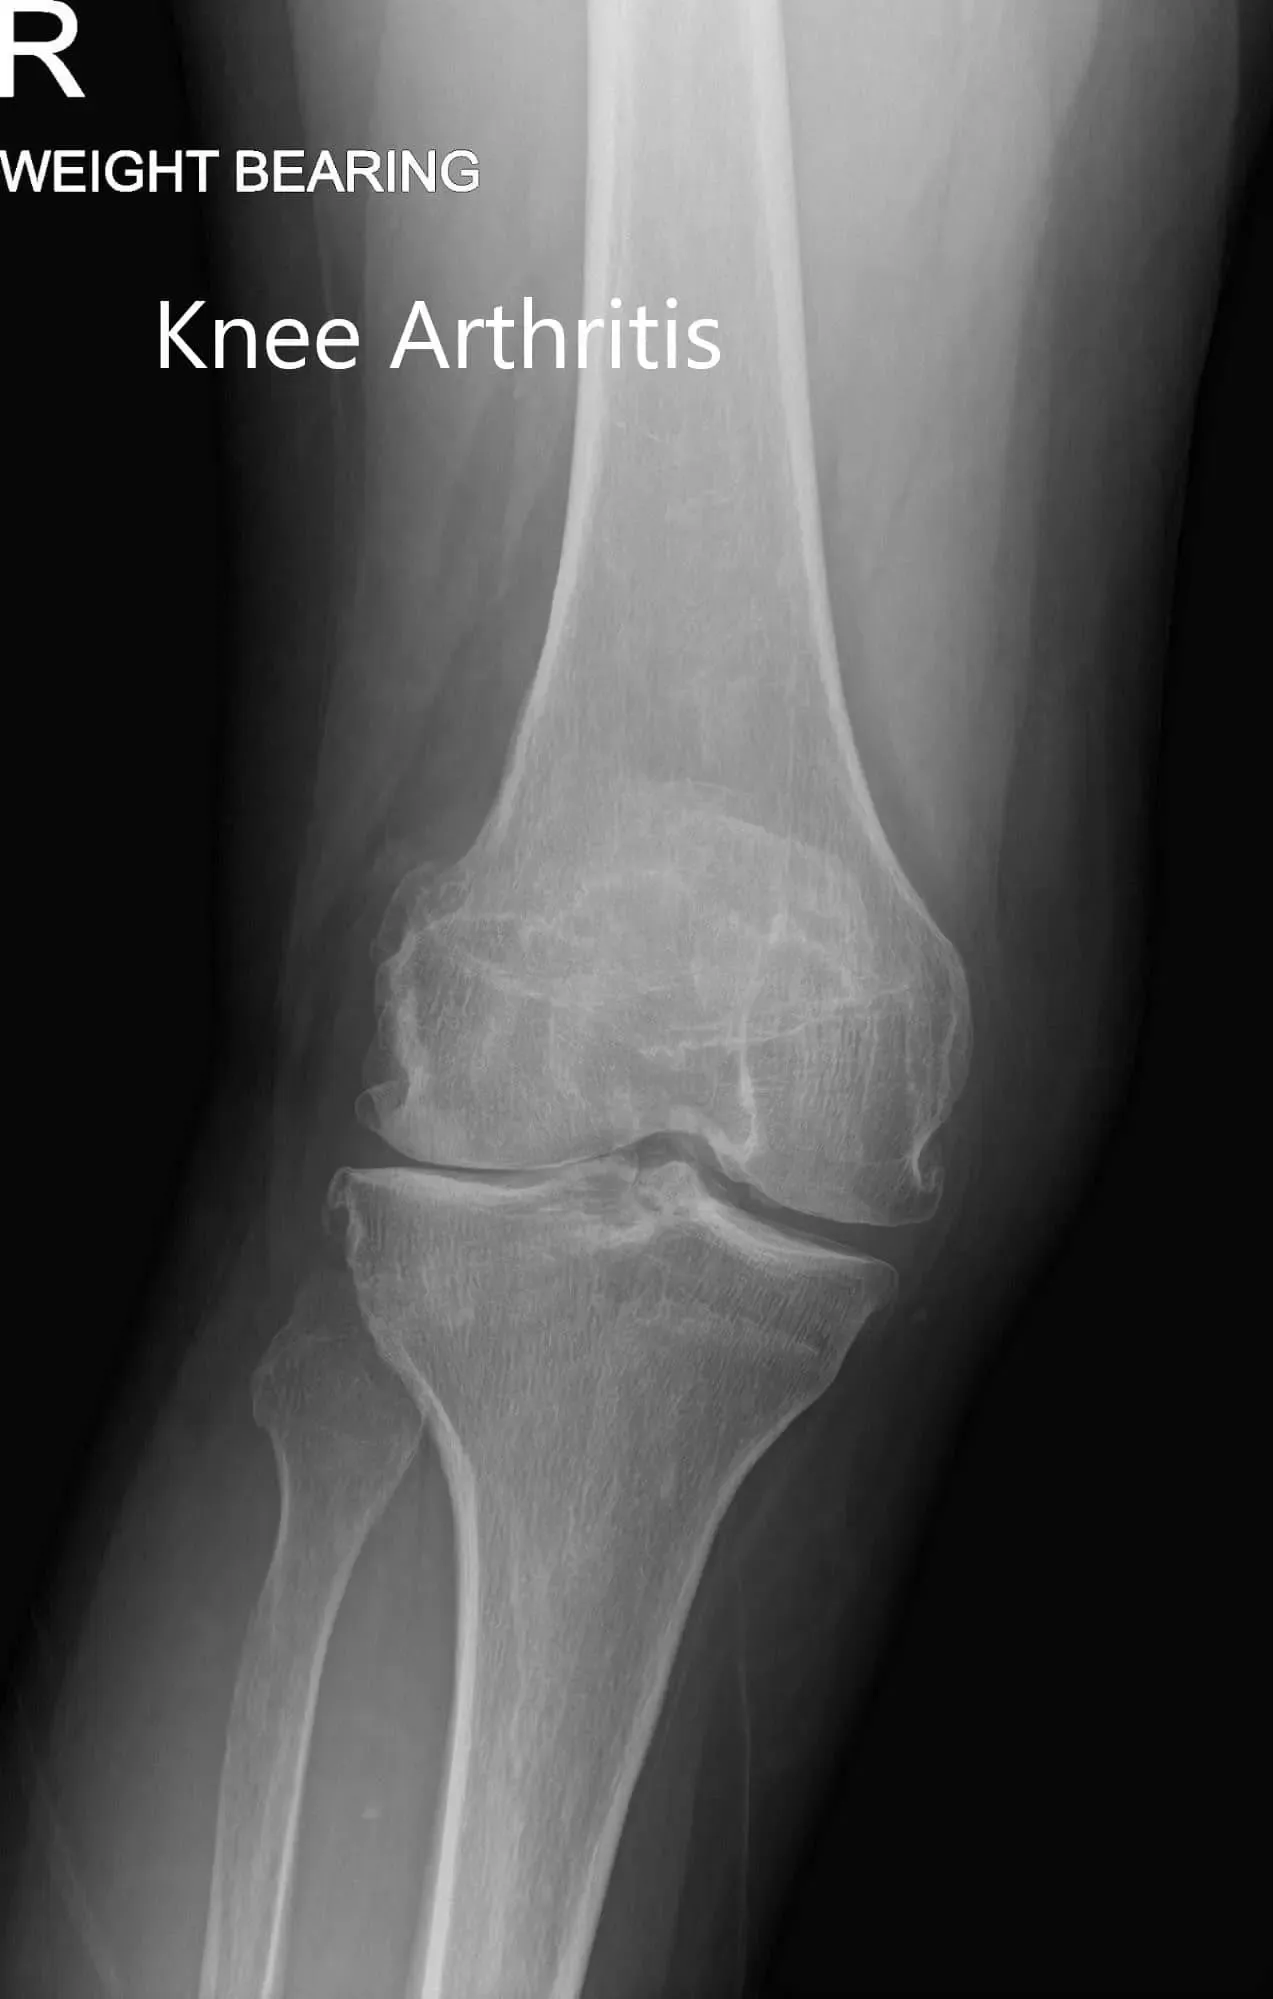

Su examen físico reveló una leve hinchazón en la rodilla derecha sin eritema ni aumento de temperatura. Había una línea articular medial y sensibilidad en la faceta rotuliana. El rango de movimiento era completo y sin deformidades. No había déficit neurológico distal. El examen de sus tobillos y rodillas bilaterales no fue nada destacable. Sus estudios de imagen revelaron una osteoartritis tricompartimental severa de la rodilla derecha.

Radiografía preoperatoria con soporte de peso que muestra la visión AP y lateral de la rodilla derecha